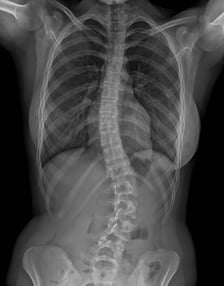

Der Cobbwinkel ist der Krümmungswinkel der Skoliose. Er wird vom Orthopäden auf dem Röntgenbild ausgemessen und in Grad angegeben. Ab 10° spricht man von Skoliose. Wenn eine Skoliose mehrere Bögen hat, hat man auch mehrere Cobbwinkel. Der Hauptbogen einer Skoliose hat in der Regel den grössten Cobbwinkel. Anhand des Cobbwinkels ist es möglich, den Verlauf einer Skoliose über die Jahre zu verfolgen.